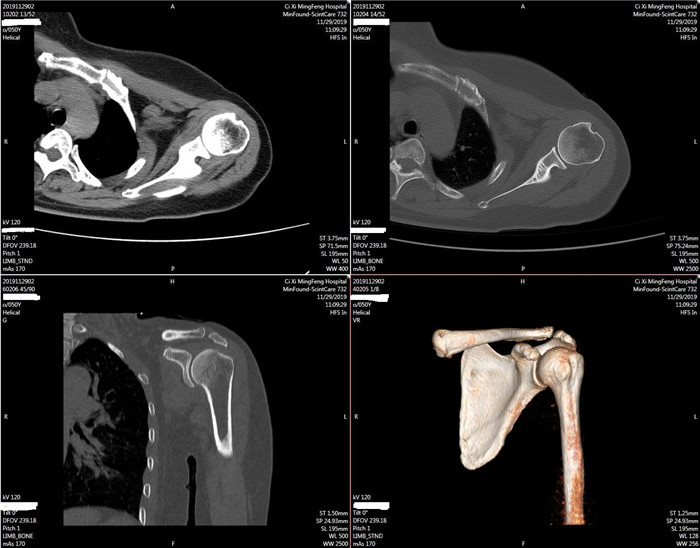

明峰CT搭載了領(lǐng)先的硬件技術(shù)平臺(tái)及系統(tǒng),強(qiáng)大的掃描能力可滿足臨床的各種要求,呈現(xiàn)更極致的細(xì)節(jié),為各臨床科室提供高品質(zhì)的圖像。薄層掃描,消除部分容積效應(yīng),提高各向同性。配合高分辨率算法,有助于細(xì)微結(jié)構(gòu)和形態(tài)學(xué)顯示。